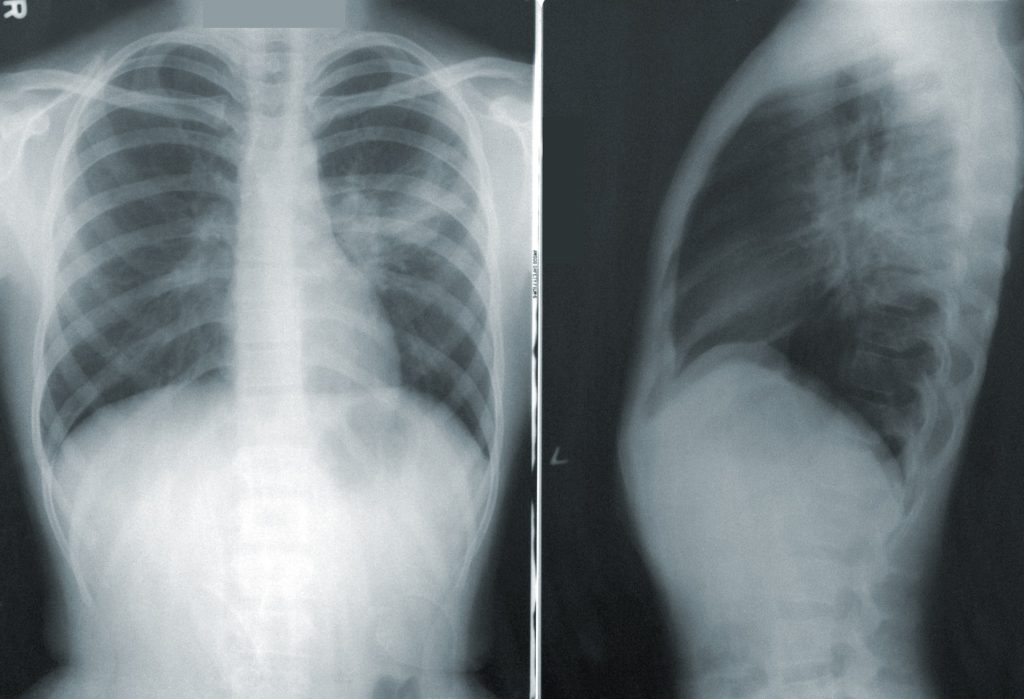

Toraxia puede identificar y caracterizar los signos patológicos sugestivos del coronavirus en las radiografías de tórax mediante el uso de inteligencia artificial.

Uno de los desafíos más grandes que han enfrentado los servicios de salud en Chile durante la presente pandemia ha sido la capacidad de analizar rápida y sistemáticamente las radiografías necesarias para detectar signos de enfermedades respiratorias tradicionales y las asociadas a la Covid-19. En ese contexto ha destacado una plataforma -hecha en Chile- la que mediante tecnología de machine learning está ayudando a los médicos a detectar infecciones asociadas al coronavirus en menos de 10 segundos.

En ambas versiones, se logra disminuir el error de diagnóstico radiológico que puede llegar a un 50% para médicos generales, debido a la baja formación en el análisis de radiografía de tórax, siendo así una herramienta para salvar vidas, ya que entrega su opinión sobre los signos patológicos encontrados, destacando con colores el nivel de magnitud y la localización de los patrones de diferentes enfermedades, solo en segundos.